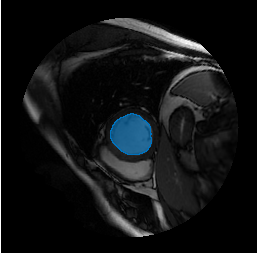

Overlay the detected object mask on the input image, and display the image with its object mask.

imMask = insertObjectMask(I,mask); imshow(imMask)